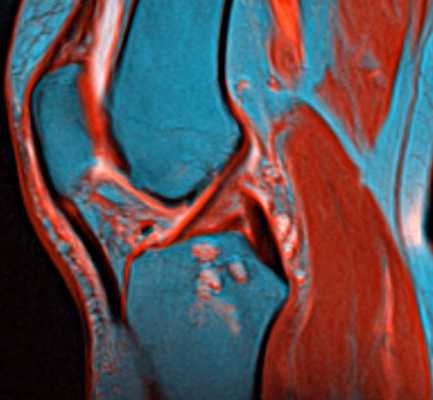

МРТ коленного сустава

МРТ коленного сустава. Т2-взвешенная сагиттальная МРТ. Цветовая обработка изображения.